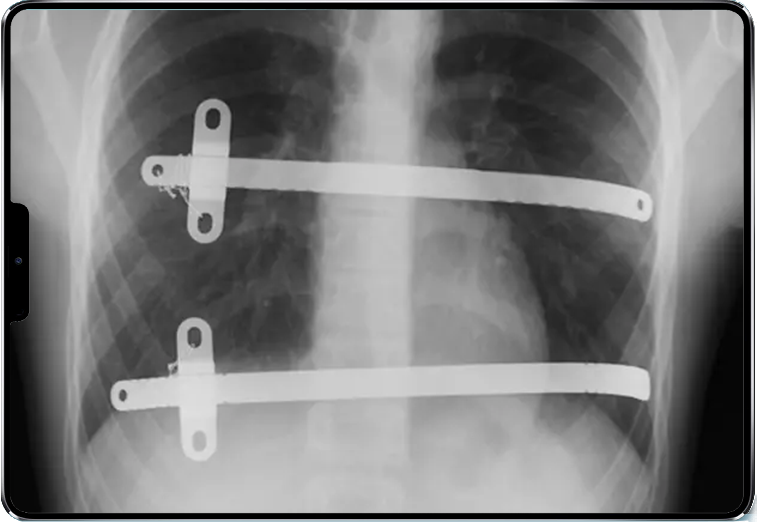

La technique de Nuss(2) est une chirurgie thoracique consistant à placer une ou plusieurs barres métalliques courbes entre le cœur et le sternum afin de repousser la paroi thoracique et de corriger la forme du thorax osseux. Elle est pertinente chez les jeunes adultes lorsque la déformation sternale est centrée, symétrique et provoque un réel retentissement fonctionnel.

Caractéristiques de la technique semi-fermée avec endoscopie :

- incisions cutanées latérales de petite taille, d’environ 5 cm de chaque côté du thorax ;

- introduction d’une ou plusieurs barres métalliques courbes préformées sous contrôle optique derrière le sternum, près du cœur ;

- mise en place parfois de plusieurs barres parallèles ou croisées ;

- rotation de 90° pour exercer une poussée antérieure sur le sternum et les côtes ;

- fixation éventuelle aux côtes par sutures ou stabilisateurs ;

- retrait de la barre 2 à 3 ans après l’implantation.

L’opération dure en général 1 à 2 heures et l’hospitalisation entre 4 et 7 jours.